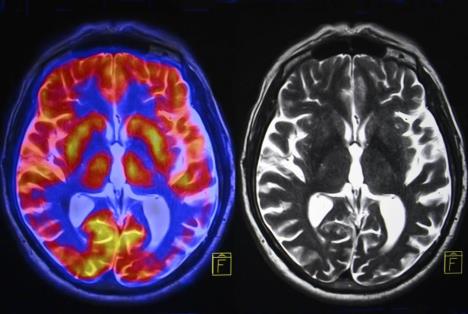

Život posle smrti postoji, bar onaj biološki, pošto pojedine ćelije ljudskog mozga ostaju aktivne nekoliko sati nakon što čovek umre, tvrde naučnici u novoj studiji, a prenosi Nacionalna geografija.

Pojedine ćelije, kako navode naučnici u istraživanju objavljenom u "Sajantifik riportu", ne samo što su aktivne, već mogu i da rastu. Radi se o glijalnim ćelijama, pratećim ćelijama u ljudskom mozgu koje ne spadaju u neuronske, već koriste za ishranu, zaštitu i potporu neuronima i oko njih obrazuju mijelinski omotač.

Ovakve karakteristike glijalnih ćelija, zbog kojih su dobile nadimak "zombi" ćelije, otkrio je tim na čijem čelu je bio Džefri Leb, šef odseka za neurologiju na čikaškom Medicinskom koledžu Univerziteta Ilinois.

- Većina studija pretpostavlja da se u mozgu sve zaustavlja kada srce prestane da kuca, ali to nije slučaj. Naši nalazi će biti neophodni kako bi se tumačila istraživanja ljudskih moždanih tkiva, pošto ovakve promene na glijalnim ćelijama do sada nisu bile precizno ustanovljene - kaže on.

- Glijalne ćelije su inflamatorne i njihov zadatak je da "počiste" okolinu posle oštećenja mozga, kao što su nedostatak kiseonika ili moždani udar - kaže Leb.

Ovakvi rezultati istraživanja mogli bi da budu veoma značajni u drugim studijama koje izučavaju uzorke mozga, jer naučnici, koji se bave istraživanjem neuroloških oboljenja, do sada nisu uzimali u obzir posmrtnu aktivnost glijalnih ćelija. Drugim rečima, istraživanja neuroloških oboljenja sada će biti znatno preciznija, navodi RT, a prenosi Sputnik.

Ali čak ni "zombi" ćelije ne žive zauvek. Istraživanje naučnika koje je predvodio Džefri Leb utvrdilo je da su glijalne ćelije aktivne 24 sata posle smrti, a da se posle toga ne mogu razlikovati od moždanog tkiva koje počinje da se raspada.